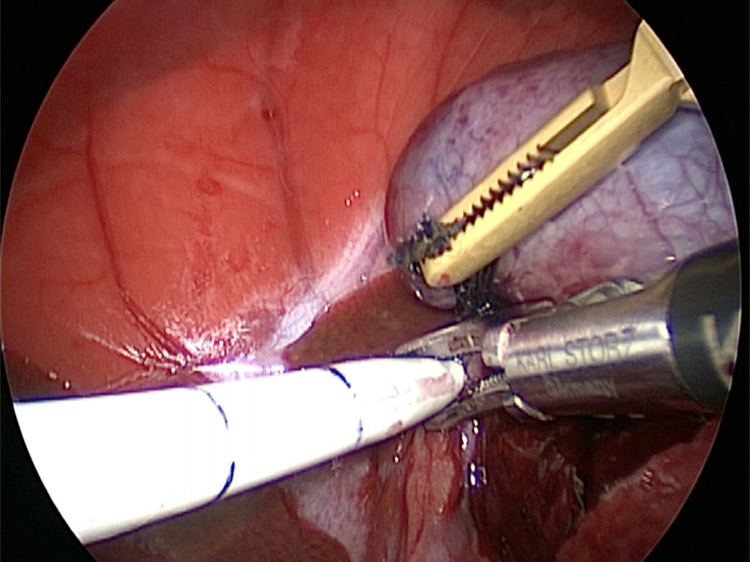

他院より紹介。胆嚢炎がひどく繰り返す嘔吐がありました。 腹膜と一部横隔膜に胆嚢ががっちりと癒着していました。 体重が2kgと体も小さかったのですが、飼い主さんの希望もあり、腹腔鏡下で手術を実施することになりました。

体の外に出すためお腹の中で袋に入れていきます。

このときに胆嚢と一緒にクリップやガーゼも回収します。そしてお腹の中をきれいにしていきます。

胆嚢の頸部に糸を通し動脈を確保しています。

胆嚢を少しずつ丁寧に肝臓から剥がしています。

回収袋にいれて体外に摘出していきます。